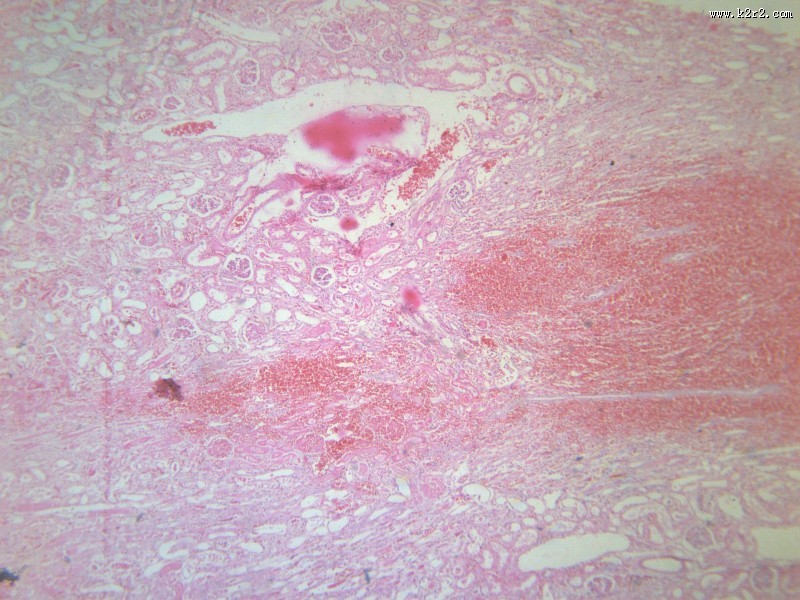

肾小管坏死 - 第4张

肾小管坏死

肾凝固性坏死

肾小管水肿

医学

显微切片